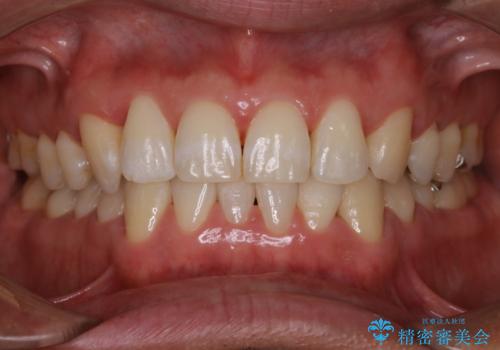

全体的な治療の開始前に着色取り